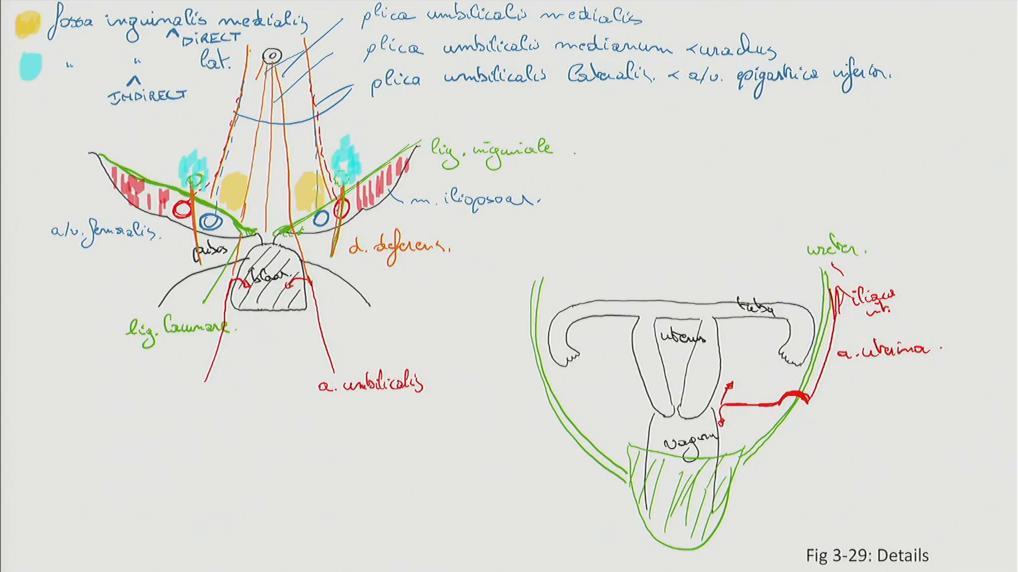

Fig 3.29a: Details

A binnenkant buikwand

navel os pubis blaas lig inguinale m iliopsoas lig lacunare a femoralis v femoralis -

plica umbilicalis medialis

plica umbilicalis medianum (= geoblitereerde urachus) -

plica umbilicalis lateralis

-

inwendige liesopening

-

fossa inguinalis medialis

-

fossa inguinalis lateralis

B baarmoeder

uterus tuba vagina blaas ureters a uterina